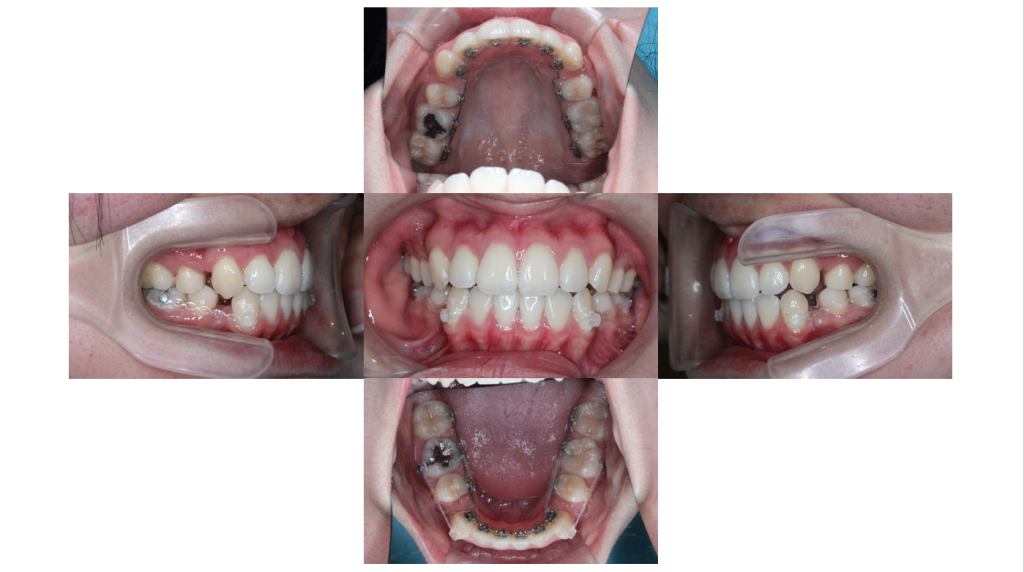

約8ヶ月経過

叢生・裏側矯正の症例上下ともでこぼこが改善され、下顎から抜歯したスペースを閉じていきます。